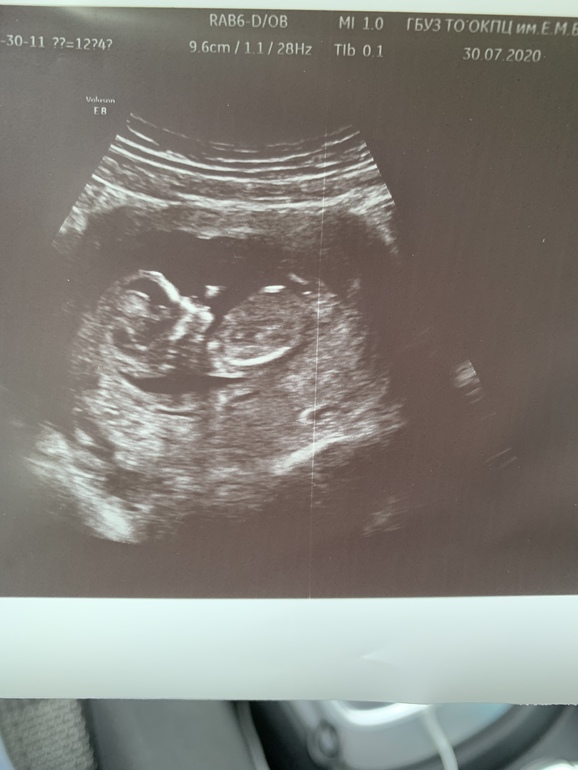

УЗИ, КТГ, доплерДержусь я и жду второго скрининга,дата которого близка к дате,когда мы планируем нашу гендерную вечеринку(которую мы приурочили к годовщине свадьбы),но все-таки скрининг на неделю раньше и не знаю,дотерплю ли я не подсмотрев.уже так интересно,кто у нас!))как думаете?)

Это почти 12 недель.